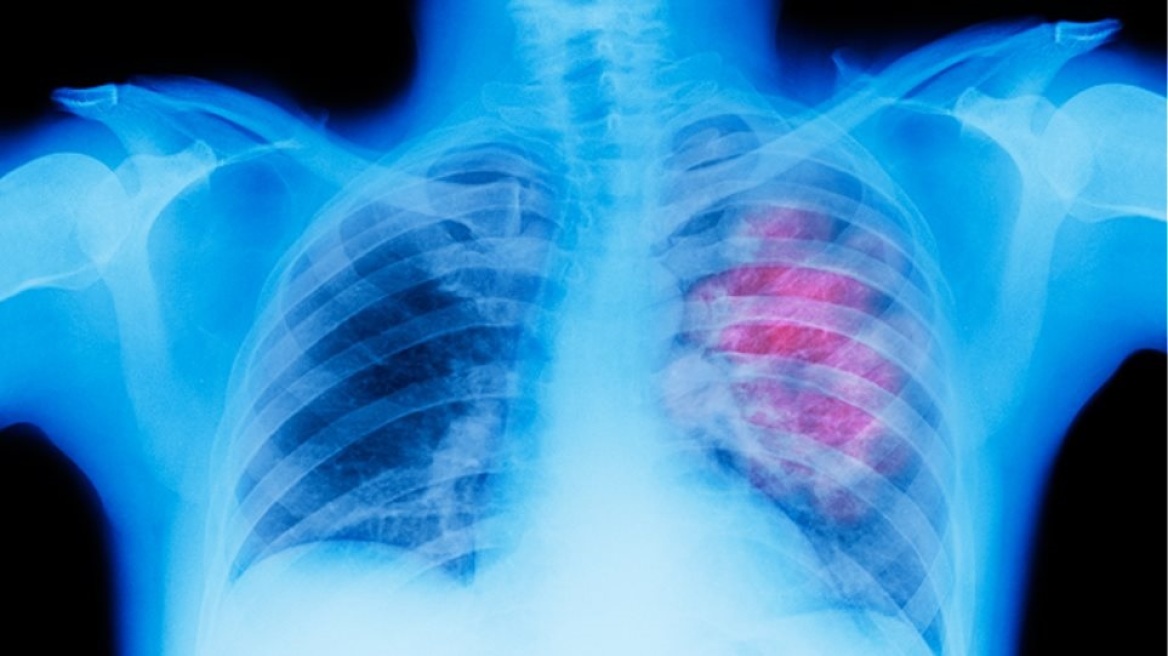

Όπως υπογράμμισαν οι ειδικοί, στη διάρκεια της εκδήλωσης για την παρουσίαση της καμπάνιας ευαισθητοποίησης του κοινού για τον καρκίνο του πνεύμονα με τίτλο «Φοράμε Λευκό» (www.foramelefko.gr, hashtag #foramelefko, http://bit.ly/foramelefko ), η ανάγκη για ενημέρωση για τη νόσο είναι μεγάλη, με δεδομένο ότι o καρκίνος του πνεύμονα αποτελεί την πιο συχνή μορφή καρκίνου στους άνδρες και την τρίτη συχνότερη μορφή στις γυναίκες. Στην Ελλάδα καταγράφονται περισσότερα από 7.000 νέα περιστατικά καρκίνου του πνεύμονα κάθε χρόνο.

Τον πιο μεγάλο μύθο για τον καρκίνο του πνεύμονα, δηλαδή ότι μόνον οι καπνιστές εκδηλώνουν καρκίνο του πνεύμονα, «διέλυσε» ο πρόεδρος του ΔΣ της ΕΟΠΕ, Διευθυντής Ογκολογικής Μονάδας «ΒΙΟΚΛΙΝΙΚΗ» Θεσσαλονίκης, κ. Ιωάννης Μπουκουβίνας. «Γνωρίζουμε πλέον πως 1 στους 9 καπνιστές θα αναπτύξει καρκίνο του πνεύμονα, αλλά και ότι ποσοστό 12% των ασθενών με καρκίνο πνεύμονα, δεν υπήρξαν ποτέ καπνιστές. Παράλληλα, είναι αποδειδειγμένο πια πως 8 στους 10 καπνιστές θα αναπτύξουν ασθένειες που σχετίζονται με το κάπνισμα π.χ. καρδιαγγειακά και αναπνευστικά νοσήματα. Επίσης, γνωρίζουμε πως ο μικροκυτταρικός καρκίνος του πνεύμονα εμφανίζεται σχεδόν αποκλειστικά σε καπνιστές» είπε ο ειδικός στην ομιλία του, τονίζοντας την ανάγκη αυτά να επικοινωνηθούν στο κοινό.